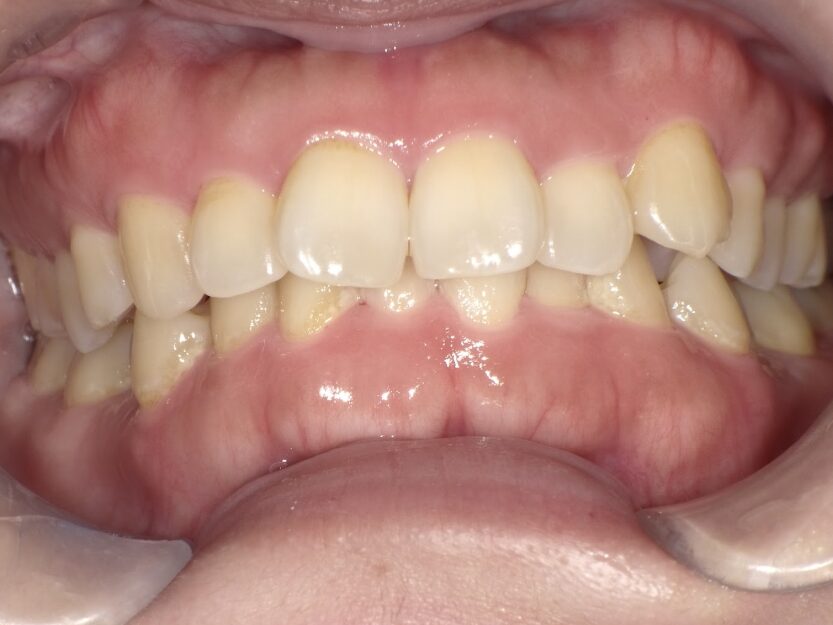

過蓋咬合

治療前

ガタガタを主訴に当院を受診され、上下前歯部に叢生(ガタガタ)と過蓋咬合(上の歯が下の歯を深く覆いかぶさっている状態)を認めました。

IPRを使用してマウスピース型矯正装置(インビザライン)を使用し過蓋咬合及び叢生の改善を行いました。